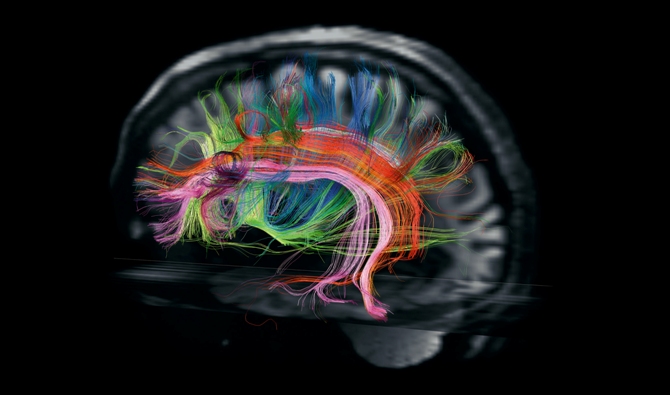

Тайните на мозъка

Текст: Карл Зимър; снимки: Робърт Кларк

Нови технологии хвърлят светлина върху най-голямата загадка на биологията: как всъщност работи мозъкът.

Ван Уедийн поглажда брадата си и се навежда към компютърния екран, прехвърляйки купища файлове. Седим в библиотека сред износени кашони със стари писма, научни списания и един старомоден диапозитивен проектор, който никой не си е дал труда да изхвърли.

„Секунда, сега ще намеря вашия мозък" - казва Уедийн.

Той съхранява на харддиск стотици мозъци - изключително подробни триизмерни изображения от маймуни, плъхове и хора, включително и от мен. Уедийн предлага да се поразходим из собствената ми глава.

„Ще посетим всички забележителности" - обещава той, смеейки се.

Това е втората ми визита в Центъра за биомедицински образни изследвания „Мартинос" в Бостън. Първата беше няколко седмици по-рано. Лежах върху масата в една скенерна лаборатория, а задната част на главата ми почиваше в отворена пластмасова кутия. Рентгенологът спусна над лицето ми бял пластмасов шлем. Погледнах нагоре към него през двете дупки за очите, докато той затягаше шлема, така че съдържащите се в него 96 миниатюрни антени да бъдат достатъчно близо до мозъка ми, за да улавят радиовълните, които той щеше да излъчва. Масата се плъзна в цилиндричната паст на скенера, а аз се сетих за „Мъжът с желязната маска".